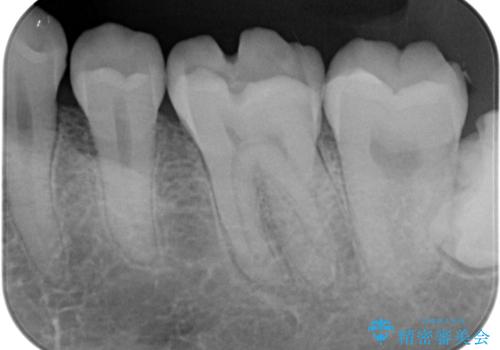

レントゲンやCTより、深くまで破折していることが分かり、抜歯が必要な状態でした。

歯槽骨の状態は良好であったため、抜歯即時埋入インプラントによる補綴治療を行うこととしました。